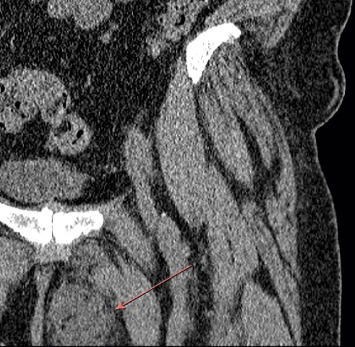

Mycobacterium abscessus is a rapidly growing non-tuberculous Mycobacterium (NTM) primarily associated with pulmonary infections, particularly in individuals with underlying lung conditions. While soft tissue infections are less common, their incidence has been increasing. These infections are challenging to treat due to inherent resistance to many antibiotics obtained through spontaneous mutation as well as physical characteristics of the microbes. The case presented here describes a 61-year-old female without obvious risk factors for mycobacterial infection who developed an intramuscular abscess over a 2-year period following a mechanical fall. Surgical resection with a complex antibiotic regimen was required based on macrolide resistance and a lack of established treatment plans for such a rare presentation. This case highlights the increasing incidence of NTM and the variable clinical presentation. Early identification with a combination of surgery and antibiotics is usually indicated to successfully manage these infections. Even without obvious risk factors, NTM infection should be considered in the presence of soft tissue and intramuscular abscesses.